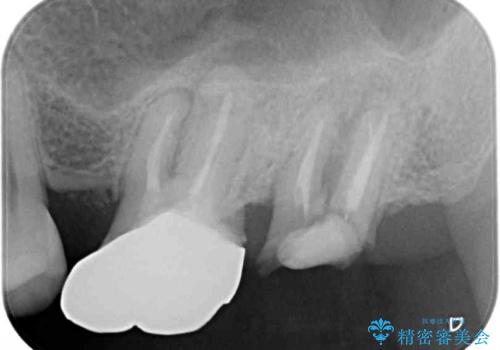

奥の歯は抜歯が必要なため、インプラント埋入による補綴治療を行うこととしました。

手前の歯は状態は良くないものの、抜歯するほどではないと判断したため、根管治療後にオールセラミッククラウンにて補綴治療を行うこととしました。

術後半年でレントゲン写真を撮影したところ、インプラント周りの骨は安定しており、根管治療を行った歯周辺の病変はきれいに改善されていました。